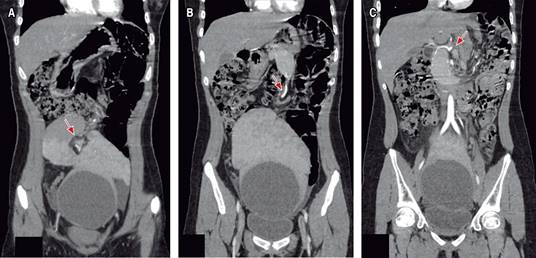

Figura 1: Tomografía abdominopélvica contrastada de cortes axiales. A) Ausencia de bazo en cuadrante superior izquierdo. B) Corte axial a nivel umbilical donde se reporta como imagen ovalada dependiente de Anexo izquierdo, desplazando útero y asas intestinales, con componente sólido (asterisco rojo) y quístico que muestra reforzamiento a la aplicación de medio de contraste, componente sólido de 121 × 43 × 90 cm y componente quístico de 90 × 90 × 91 mm (se puede observar imagen correspondiente a bazo por características anatómicas con presencia de un quiste). C y D) Se observa componente quístico (asterisco azul) que se encuentra en hueco pélvico.

Figura 2: Tomografía abdominopélvica contrastada en la cual podemos realizar seguimiento de arteria esplénica hasta su origen en el tronco celíaco. Diferentes cortes en donde se muestra con flecha roja el seguimiento de la arteria esplénica.